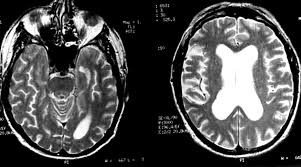

Differential Diagnosis Of Temporal Lobe Lesions With Hyperintense Signal On T2 Weighted And Flair Sequences Pictorial Essay

Differential Diagnosis Of Temporal Lobe Lesions With Hyperintense Signal On T2 Weighted And Flair Sequences Pictorial Essay from www.scielo.br

The differential diagnoses include limbic encephalitis (paraneoplastic), gliomatosis cerebri, and status epilepticus. Ventriculitides) refers to inflammation, usually due to infection, of the ependymal lining of the cerebral ventricles. For a general discussion, and for links to other system specific manifestations, please refer to the article on coccidioidomycosis. Herpes simplex (hsv) encephalitis is the most common cause of fatal sporadic fulminant necrotising viral encephalitis and has characteristic imaging findings. Bilateral temporal lobe t2 hyperintensity refers to hyperintense signal involving the temporal lobes on t2 weighted and flair imaging. For a general discussion, and for links to other system specific manifestations, please refer to the article on hydatid disease. Given the history of fever and seizures coupled with the mri findings of bilateral mesial temporal lobe changes, herpes encephalitis requires clinical consideration. It is most often due to meningitis. Multilocularis.the larval stage is the cause of hydatid disease in humans 1. Spinal hydatid disease is an uncommon manifestation of hydatid disease, caused by the larval stage of echinococcus granulosus, or less commonly e. Terminology cerebritis is essentially the same as encephalitis except that it is used to denote brain par. It is a common finding on brain mri and a wide range of differentials should be considered 1. It is usually bilateral but asymmetrical.

The changes spare the basal ganglia, a feature which is helpful in distinguishing an mca infarct with hemorrhagic transformation from herpes simplex encephalitis, the diagnosis in this case. Hse may result from primary infection or reactivation from latency, and it frequently involves frontal or temporal lobes, as well as the brain stem. Herpes simplex (hsv) encephalitis is the most common cause of fatal sporadic fulminant necrotizing viral encephalitis and has characteristic imaging findings. It is usually bilateral but asymmetrical. The differential diagnoses include limbic encephalitis (paraneoplastic), gliomatosis cerebri, and status epilepticus. Two subtypes are recognized which differ in demographics, virus, and pattern of involvement. Given the history of fever and seizures coupled with the mri findings of bilateral mesial temporal lobe changes, herpes encephalitis requires clinical consideration. Spinal hydatid disease is an uncommon manifestation of hydatid disease, caused by the larval stage of echinococcus granulosus, or less commonly e. Multilocularis.the larval stage is the cause of hydatid disease in humans 1. The differential diagnoses include limbic encephalitis (paraneoplastic), gliomatosis cerebri, and status epilepticus. Herpes simplex encephalitis (hse) is the most common form of viral sporadic encephalitis and, when left untreated, has a mortality rate of 70% (3, 22). This patient went on to have hsv encephalitis proven on csf pcr. Bilateral temporal lobe t2 hyperintensity refers to hyperintense signal involving the temporal lobes on t2 weighted and flair imaging.